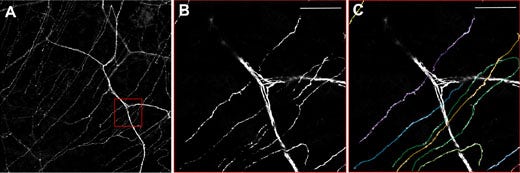

使用带有黄色荧光蛋白标记神经纤维的转基因小鼠(thy1-YFP小鼠),可以利用奥林巴斯 FV10i进行角膜神经离体观察。图3显示为基底神经丛较大的基质神经和非常细的神经。但是,角膜的细胞结构较为复杂。6 如图4所示,该神经丛靠近Bowman层,由穿透的A-delta纤维形成,并具有基底下朝向。Baltrusch教授评论说:“基底下神经对损伤非常敏感,可以在糖尿病人和动物中发现这类损伤。”将新技术与旧技术进行比较,并分析了小鼠皮肤标本,由于存在更多的AGEs受体,因此发现角膜神经更容易受到影响。

图3:thy1-YFP小鼠角膜中的神经元。

A)概述显示基底神经丛较厚的基质神经和较细的神经。

B)放大红色框,C)定量单个的基底下神经。使用FV10i,60X油浸物镜。比例尺50μm。